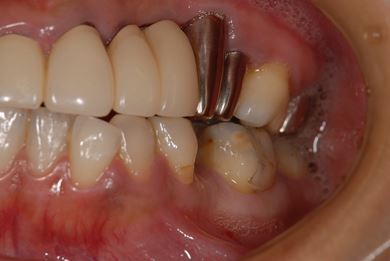

インプラントの症例写真 IMPLANT

| 主訴 | 以前治療した歯の歯ぐきから出膿。他の歯科でインプラントかブリッジしか方法がないが、骨の状態からインプラント治療は無理かもしれないと言われたことに不安を感じ、セカンドオピニオンを求めて来院。 | ||||||||||||||||||||||||||||||||

| 治療方針 | 保存不能の歯を抜歯し、インプラント治療にて機能的・審美的回復を行う。 | ||||||||||||||||||||||||||||||||

| 治療内容 | インプラント1本、ハイブリッドセラミッククラウン1本 | ||||||||||||||||||||||||||||||||